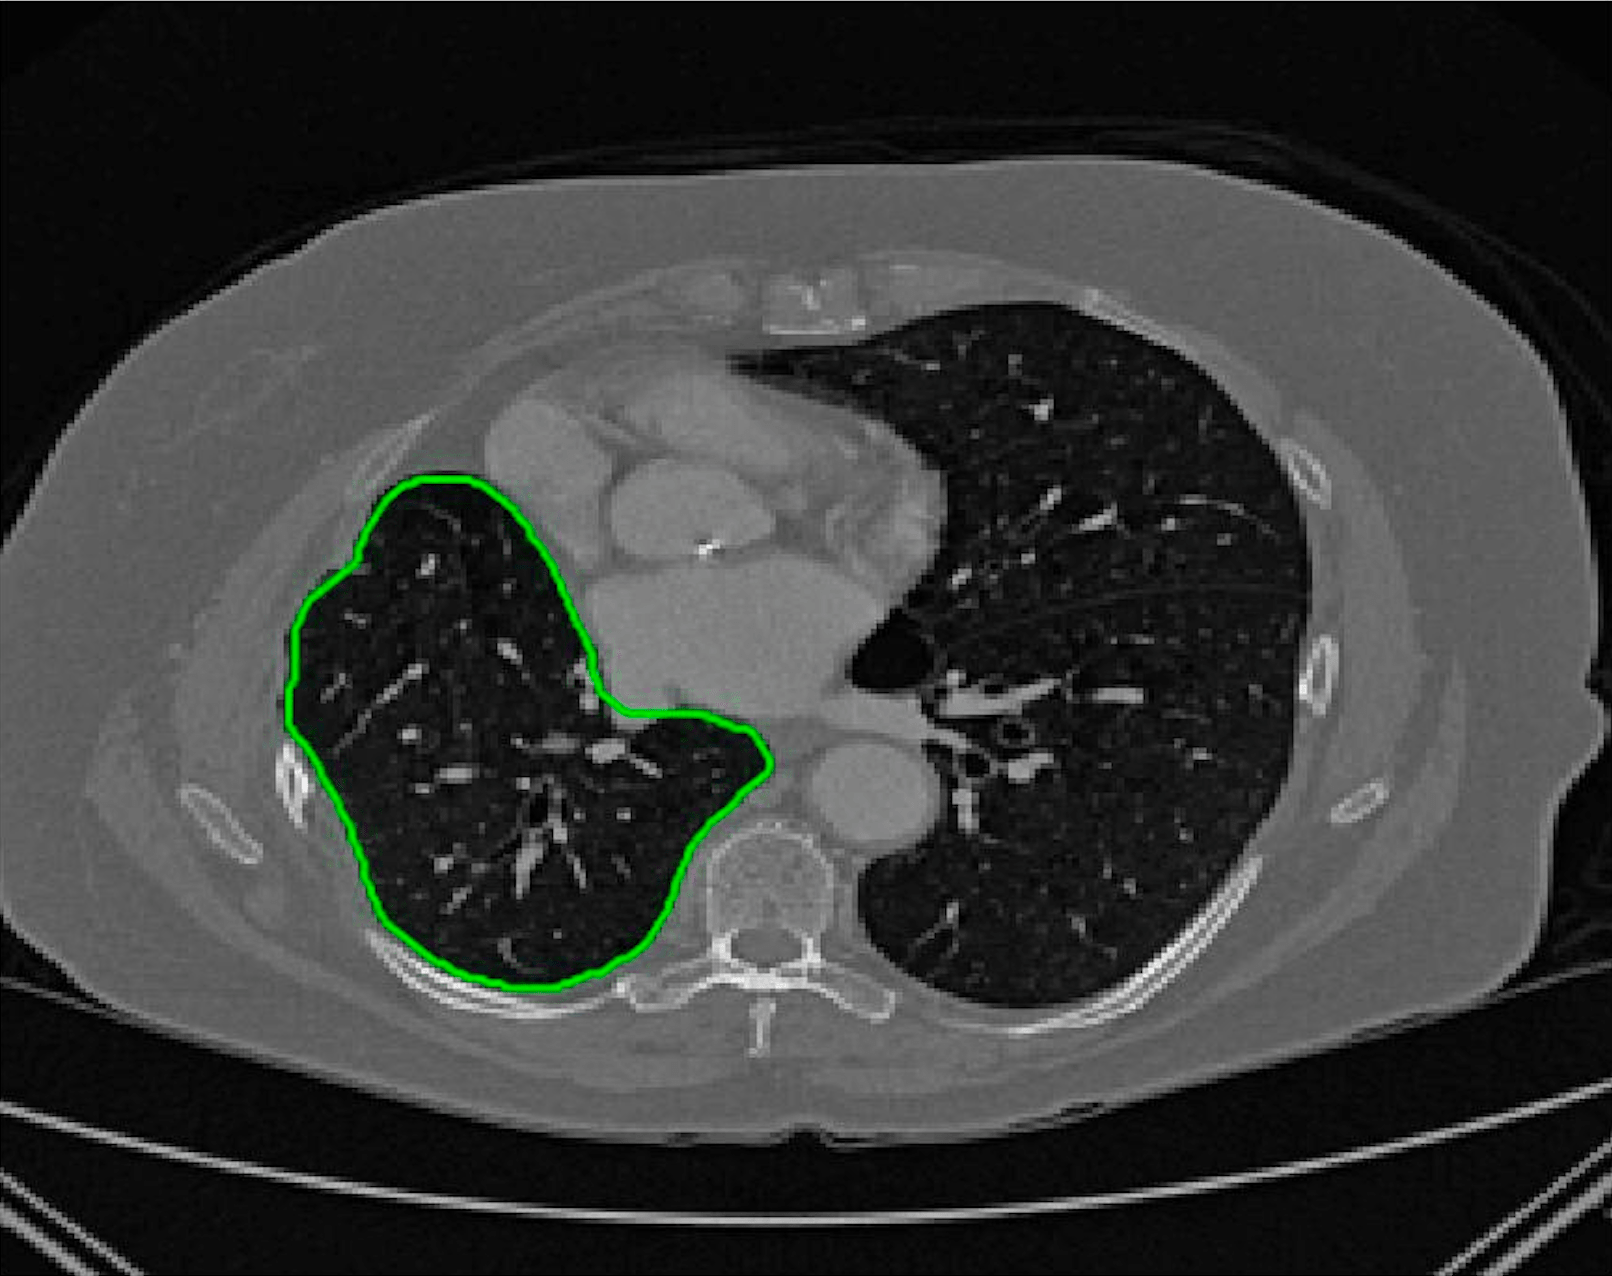

Test Images. We will perform initial tests on the images shown in Figs. 5–7. We have provided the ground truth and initialisation used for each image. Test Images 1–3 are synthetic, Test Image 4 is an MRI scan of a knee, Test Images 5–6 are abdominal CT scans, and Test Images 7–9 are lung CT scans. They have been selected to present challenges relevant to the discussion in §2. We focus on medical images as this is the application of most interest to our work. In the following we will discuss the results in terms of synthetic images (1–3) and real images (4–9). We also test the proposed approach on a larger data set of 30 CT images (a sample of which is presented in Fig. 18), comparing against existing selective methods detailed in §3.

Real Images. In Fig 12 we present results for Test Images 4–6. Here, the proposed model performs in a similar way to its competitors because these images are more typical selective segmentation problems in the sense that there is a clear distinction between the foreground and background intensities. In particular, the values in each case are: Test Image 4 , Test Image 5 , and Test Image 6 . It can be seen that the proposed model is competitive compared to previous approaches. The performance is quite poor for Test Image 5, but is arguably still the best for this challenging case. In Fig. 13 we present results for Test Images 7–9. Here the proposed model outperforms previous approaches significantly for each image. This is mainly due to the type of image considered. Specifically, the true intensities are: Test Image 7 , Test Image 8 , and Test Image 9 . The proposed model is capable of achieving results where , with other models failing completely in these cases.